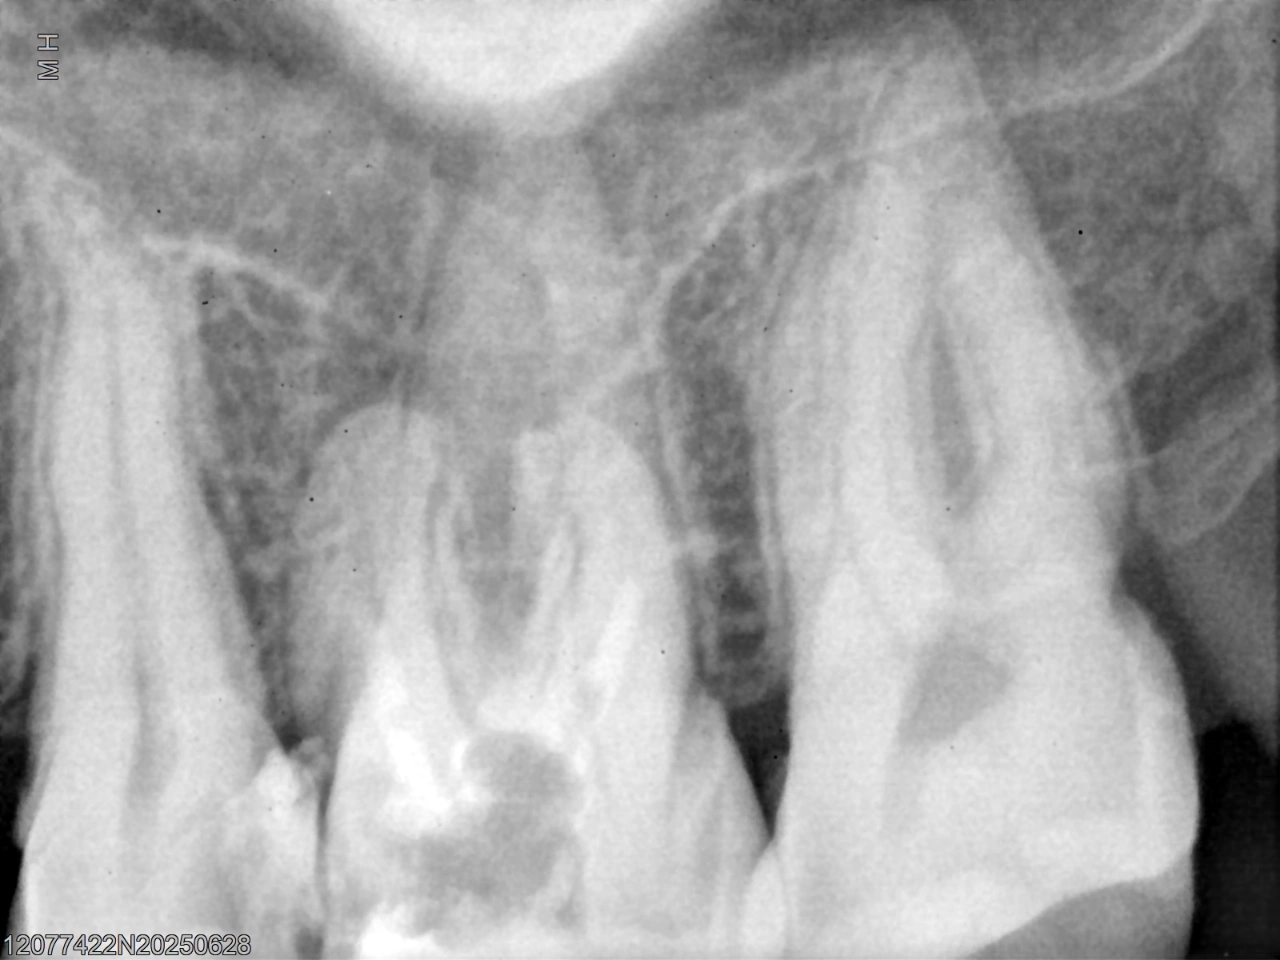

Pre-operative radiograph showing short and inadequate gutta-percha obturation.

Case Overview: This case involved the non-surgical retreatment of a previously RCT U6 presenting with inadequate obturation. Radiographic examination revealed short and poorly compacted gutta-percha, compromising the apical seal and long-term prognosis.